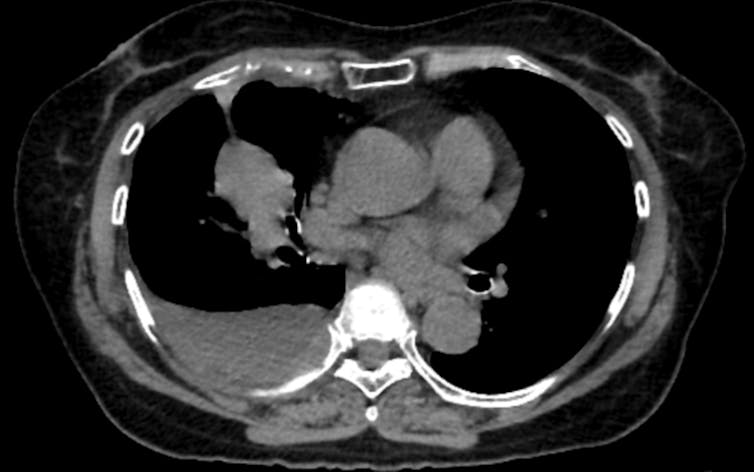

Coronary artery calcium, or CAC, is probably the best demonstration of what opportunistic screening can accomplish. When calcium builds up in the walls of the coronary arteries, it reflects underlying atherosclerosis, the disease process behind most heart attacks. CAC scoring is one of the strongest predictors of future heart attacks, and it adds predictive information beyond what traditional risk calculators provide.

Dedicated cardiac CT scans can measure this calcium precisely. So can a standard lung cancer screening CT, if someone takes the time to look. Studies have found that calcium measurements from lung screening CTs agree closely with those from dedicated cardiac scans, meaning the information is there even when the scan was not designed for cardiac evaluation.

That overlap matters because roughly 19 million noncardiac chest CTs are performed each year in the United States. Every one of those scans passes through the heart. The presence of calcium is visible in the images – yet studies find that when CAC is present, radiologists report it in fewer than half of cases.